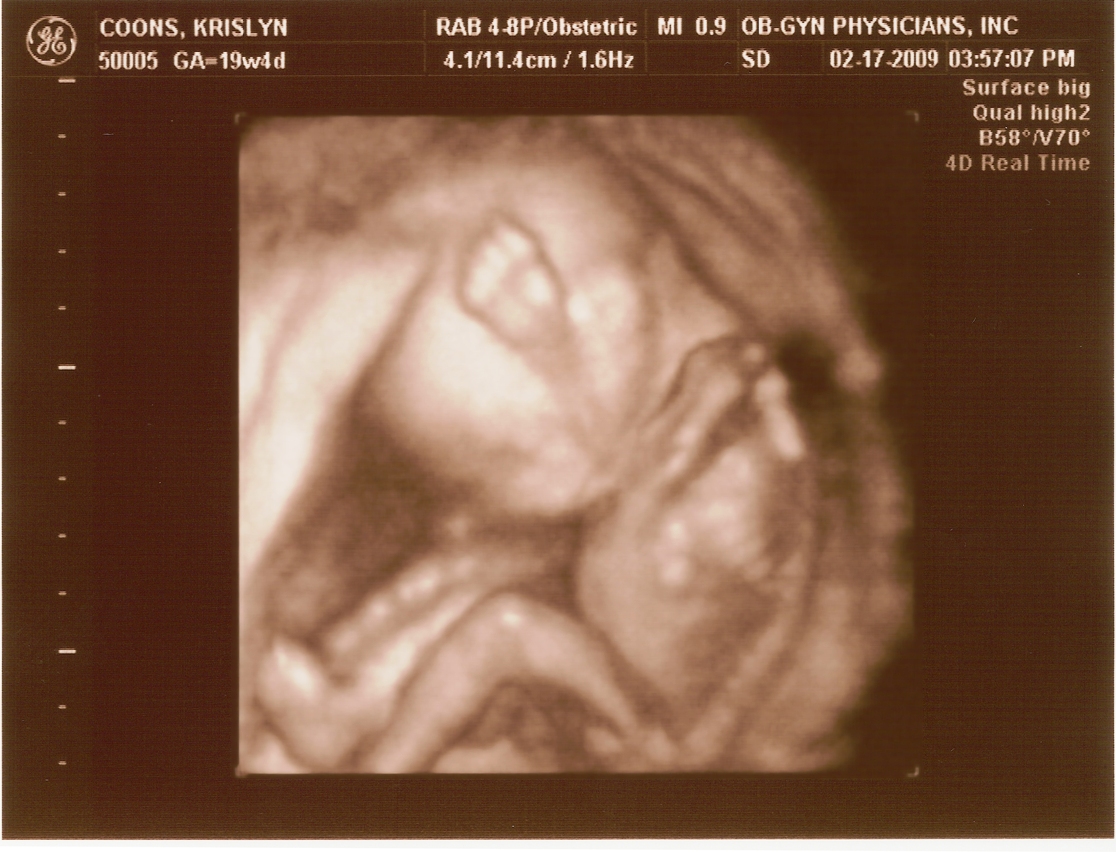

2.17.2009

First ultrasound! The baby measures right on target and appears to be developing normally. All looked and sounded great. Krislyn is finally gaining some baby weight too!

20 weeks -

20 weeks